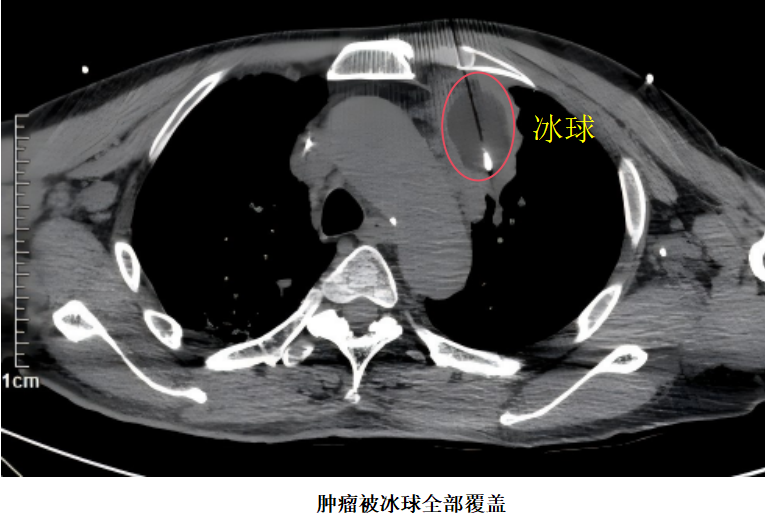

此次手术由胸外科副主任邹耀罡主任医师主刀,陈敏副主任医师与护士长杨丽华副主任护师组成的专业团队协同开展。术中,团队凭借丰富的临床经验和精准的操作技巧,在CT实时影像引导下,将直径约2mm的康博刀消融针精准置入肿瘤靶区,通过两个循环的“深度冷冻-主动复温”治疗——先将病灶温度降至-196℃的超低温,再快速升温至85℃,形成的“冰球”完整覆盖整个肿瘤病灶,实现对肿瘤组织不可逆的精准损毁。整场手术耗时短、创伤小,患者术中生命体征平稳,顺利完成,无并发症出现。术后,患者恢复良好,生活质量明显提升,一家人对治疗效果十分满意。